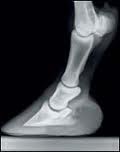

Contextual Perspective on Orthotics, Splints, and Braces

The recent post by Leonid Blyum “Analytical Review: Cerebral Palsy and Forceful Devices-Orthoses, Splints, Braces” raised a number of fundamental important points regarding the use of “devices of external support”. One particular comment prompted some significant questions which then lead to some more evaluation and thought. Without going into detail about the actual thought process, I will simply get right to the point.

There seems to be a great deal of consensus regarding the benefits of the implementation of orthotics, braces, and splints. In fact, it is without question a “staple” protocol for almost every issue of mild to severe distortions of the feet. It goes without question that some form of AFO, KFO, lift, etc will be implemented as part of the rehabilitation plan. It isn’t my intention to debate “do they work or don’t they”…this question is far too simplistic and, quite honestly, a naïve way of approaching the topic. My intention is simply to take a step (or two) backwards and attempt to gain some perspective on the more fundamental question: “are these devices doing what I intend them to do?” To be precise, are they “fixing the feet”…are they preventing any further distortion…and are they creating a more “harmonious” environment for the user? These types of questions are either never asked or simply assumed to be yes, yes, and yes. Therefore, I would like to propose that the implementation of these devices be put into proper CONTEXT. By definition, my opinion as to their “therapeutic value” is completely dependent on the context they are being prescribed. The proper context is clearly explained in the video, therefore I won’t go into detail but I will expand on a very interesting analogy that was brought up that will offer some useful insight into what I have called “Contextual Perspective”.

If you accept this concept, then you must also accept that achieving biotensegral equilibrium in a simple joint is far simpler than achieving biotensegral equilibrium in a complex joint. If we look at an x-ray of a horses foot, we can easily see that the complexity of the horse’s “foot” (or hoof, to be precise) is relatively simpler than that of the human foot.

Now we get to the human foot. When put into perspective, it is an absolute marvel of engineering. The human foot has 28 bones in it, therefore it has 84 separate potential planes of movement. This would most certainly deserve the classification of “complex”.

It’s complexity can be explained by evolution…we are biped and therefore have “two less points of contact with the ground”. Our horse, canine, and feline friends have the advantage of having four…therefore our 2 feet must be highly adaptable, sensitive, and capable of not only providing a stable platform , but allowing for multiple micro levels of movement that ultimately define our high level of agility.

What does all this mean and where does it fit into the issue of orthotics, splints, and braces??! If you’ve managed to get this far, then you are definitely worthy of some clarity! Given the obvious complexity of the human foot, it is somewhat naïve to assume that ANY adjustment at one SINGLE point of movement will produce any significant “improvement” in the condition of the foot. It is analogous to winning the lottery…yes, you may be extremely lucky and get the singular point of conflict that resolves all of your problems. However, the reality is that this is highly unlikely. Therefore my professional opinion as to the use of orthotics to “reduce distortion and improve the condition of the foot” currently remains highly skeptical at best. However, there is definitely a rationale for their use in improving comfort and reducing risk of further injury.

This statement can be explained as such: When braces are placed on the human foot, you essentially “block” the majority of the freedom within and “downgrade” the foot to a hoof. Obviously having a functional “hoof” is more productive than a distorted and painful foot. This is precisely what I mean by CONTEXTUAL PERSPECTIVE. It is also important not to stop there in this “contextual thinking”. The rest of the human body is designed with the idea that a “complex foot” is underneath…therefore, if we switch out a foot for a simpler “hoof”, there is a significant change in the force transmission to the knee and hip. Essentially, a significant amount of stress that was previously absorbed and distributed through the foot now bypasses it completely and impacts the knee and hip further up…keep this in mind when designing your treatment plan!!